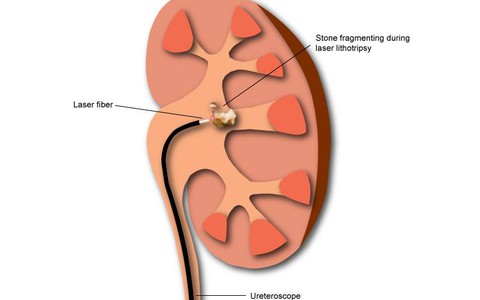

Tại các trung tâm niệu khoa, bệnh sỏi đường tiết niệu chiếm từ 2/3 đến 3/4 trong các bệnh về đường tiết niệu.